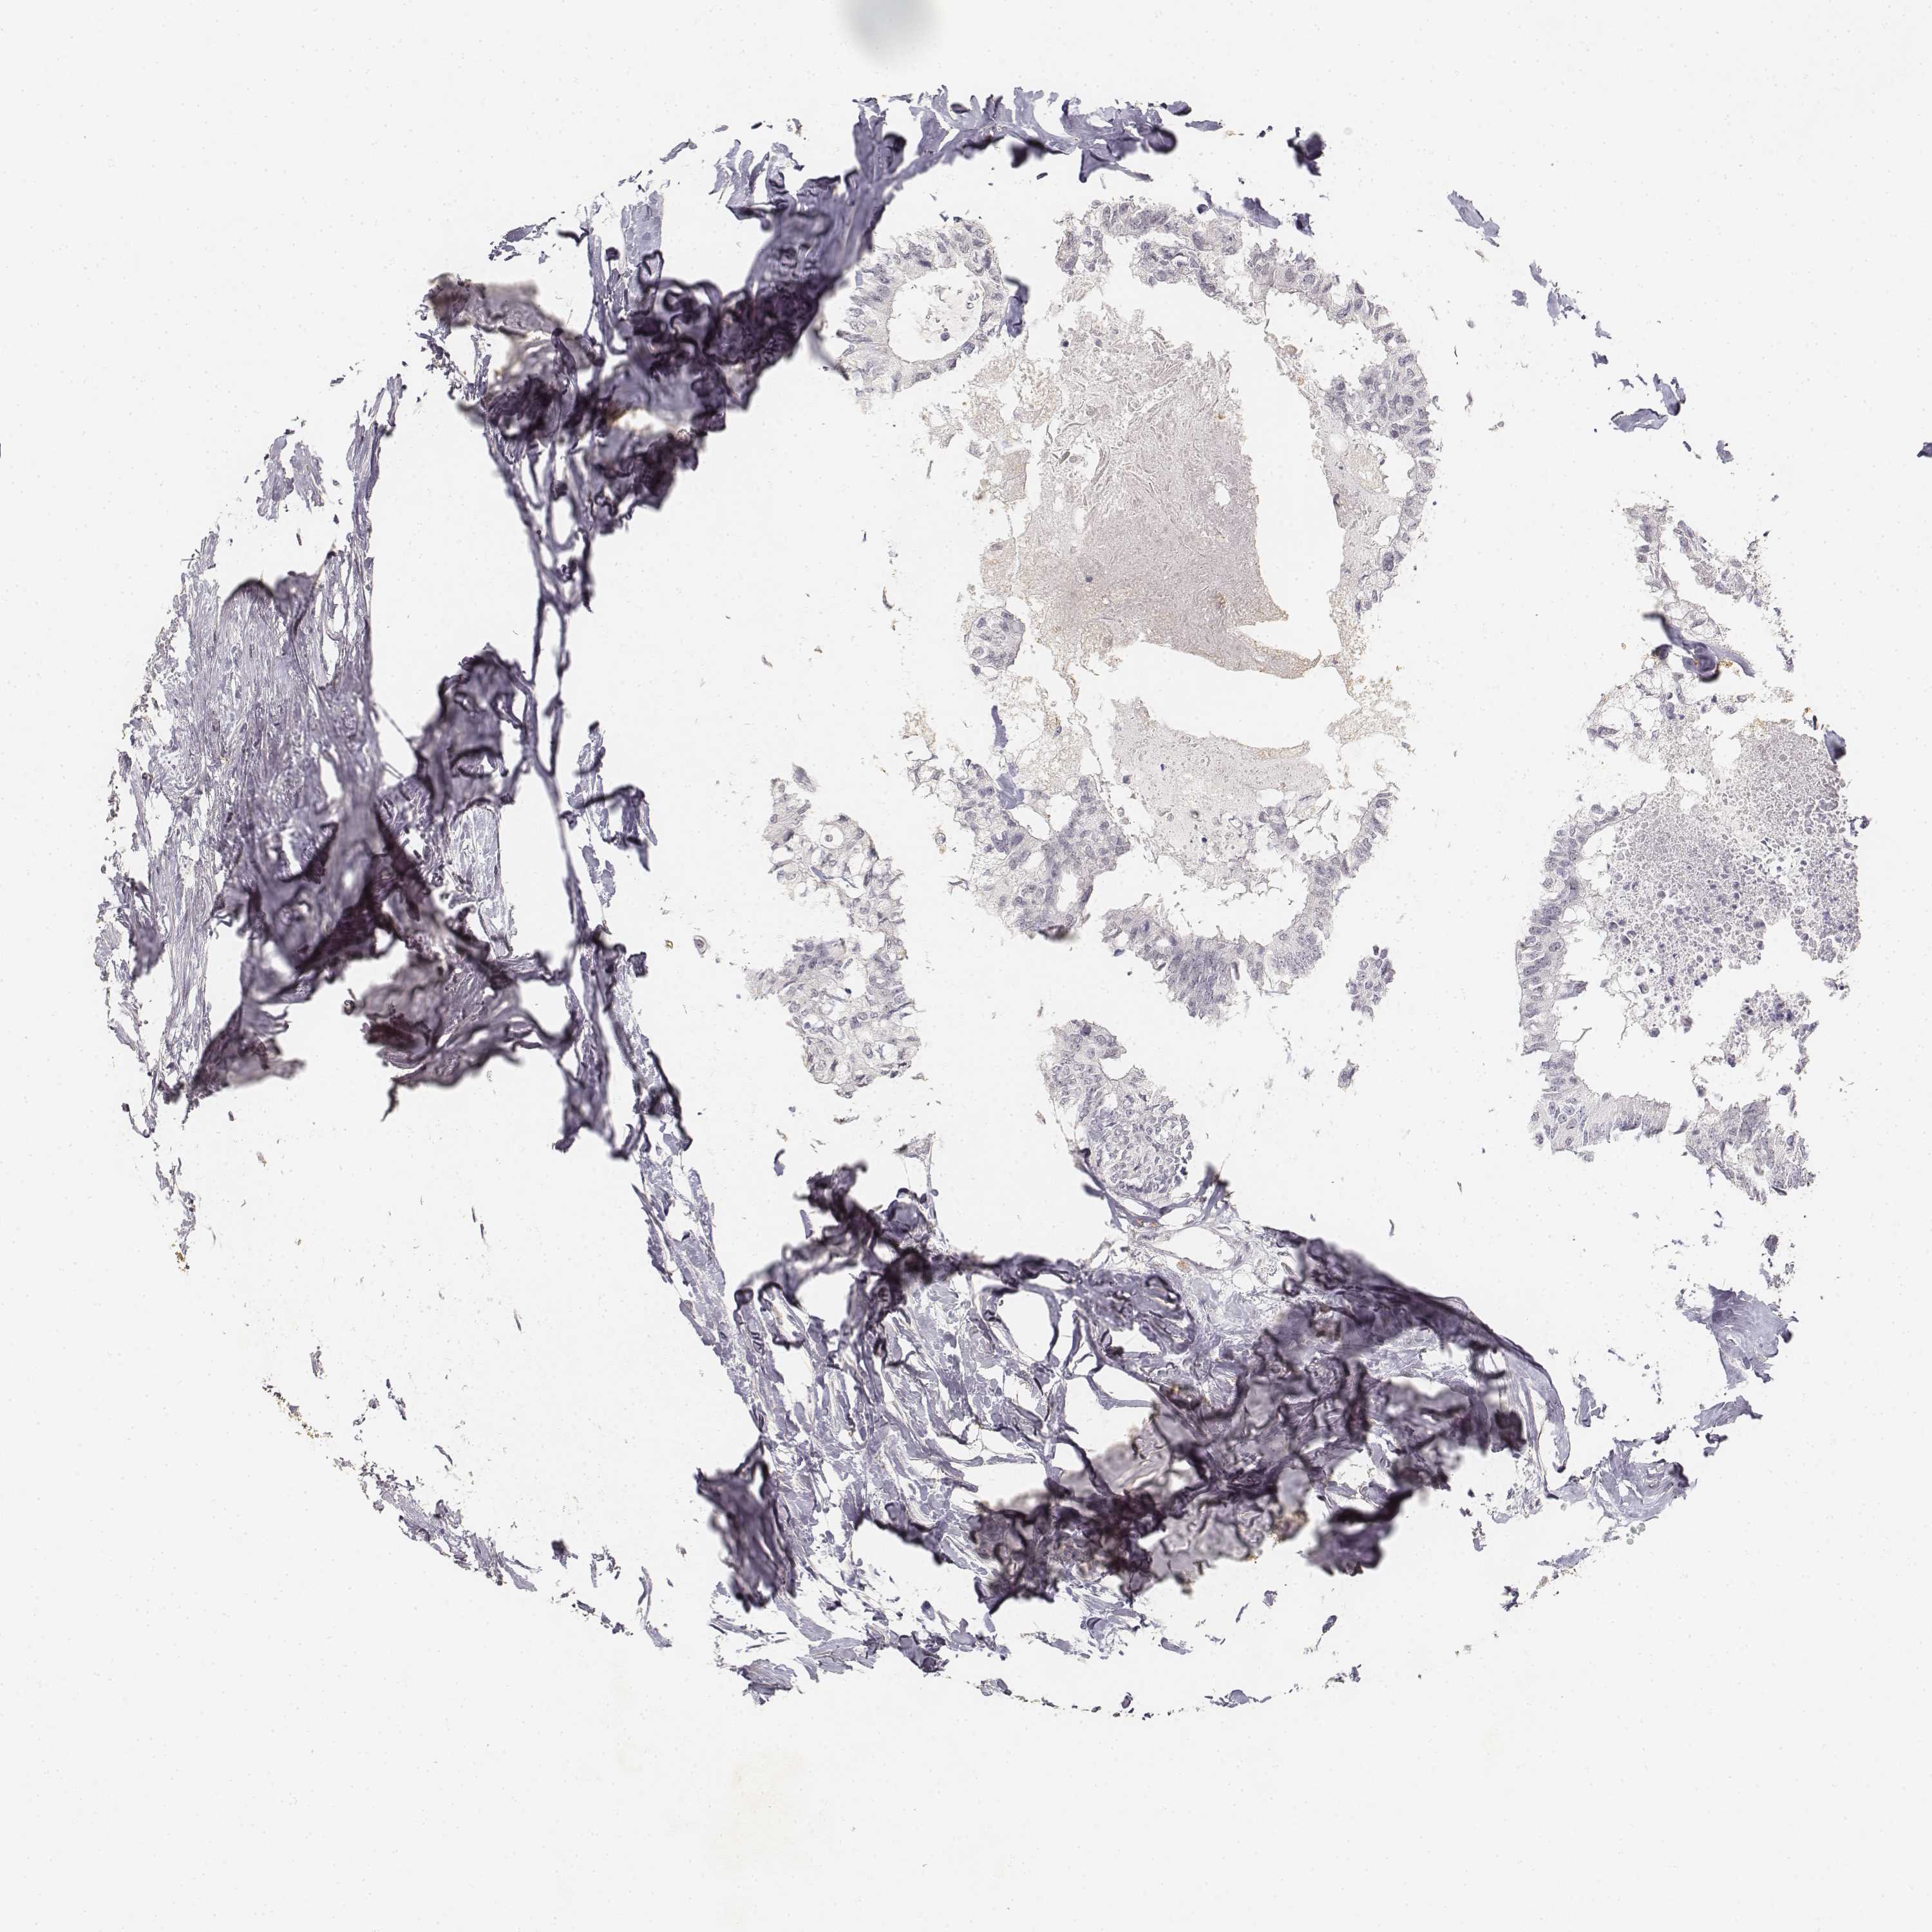

Colorectal cancer

Colon adenocarcinoma